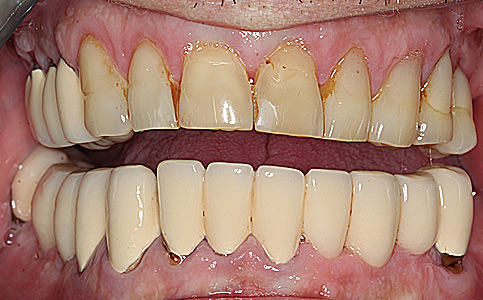

Pacjent zgłosił się do naszej kliniki ponieważ marzył o pięknym uśmiechu. Jego metamorfoza była wielospecjalistyczna. Pierwszym etapem było leczenie biologiczne, następnie uzupełnienie braków zębowych implantami oraz wykonanie koron pełnoceramicznych na zęby górne. Dzięki temu Pacjent odzyskał pewność siebie i zdrowy uśmiech.